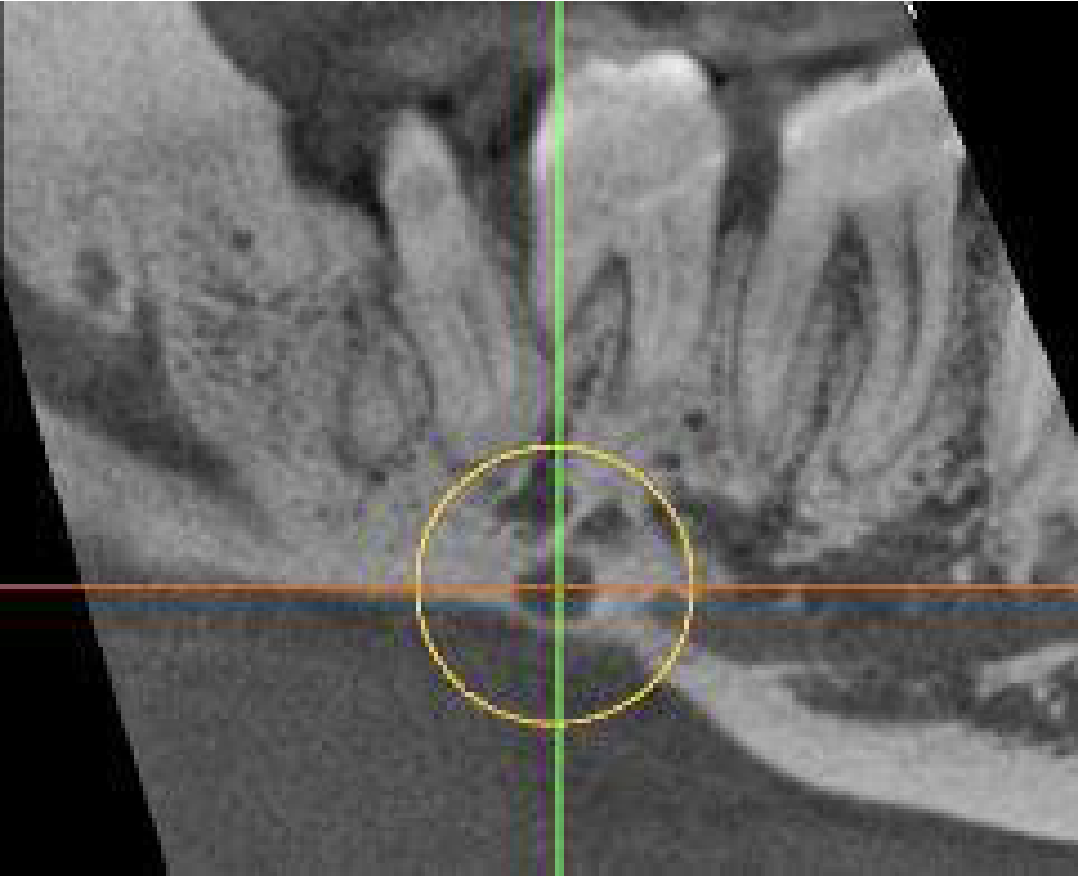

In the lingual cortical plate below the LR7 is a well-defined unilocular radiolucency, 4mm wide with loss of the external surface of the cortical plate and continuous with the bone marrow space. It is very close to the mandibular canal and its inflammation could cause pain.

Rarely, a finding such as the radiolucency in the LR7 region could be a serious lesion such as a multiple myeloma and further follow up would be recommended with an oral surgeon.